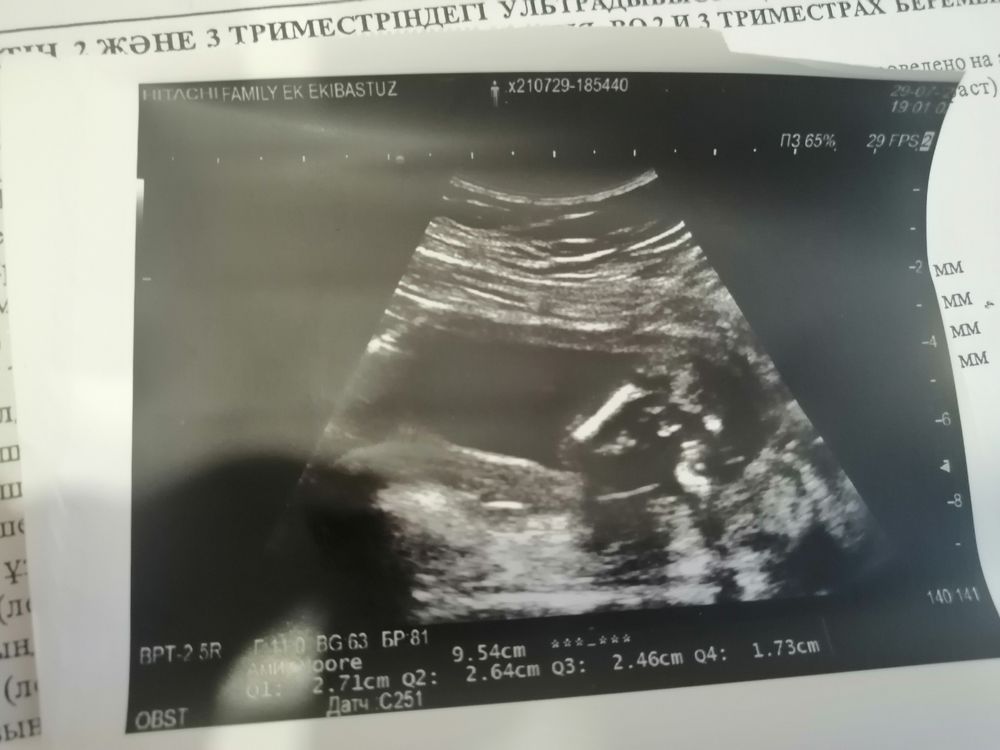

Мальчишка))) снимок попы и хозяйства)))

Ritik, да, а где Вы увидели? Объясните мне пожалуйста, вот здесь?! Изображение

Настя Литвинова, ну да, по бокам ножки, а между краник 😅